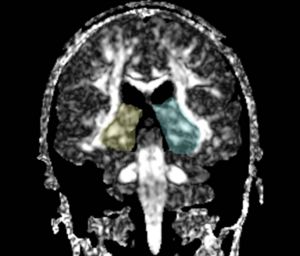

We apply fiber tractography to quantify fornix Fractional Anisotropy (FA) in schizophrenia. Two ROI method (shown in the figures) were used to extract left and right fornix in 34 chronic schizophrenia subjects and 40 matched controls, and mean FA along the entire tract was extracted separately for the left and the right sides and compared between groups. Preliminary data indicate bilateral decreased FA in the fornix of schizophrenics.

ROIs for Tractography

Fornix roi1.jpg Fornix roi2.jpg